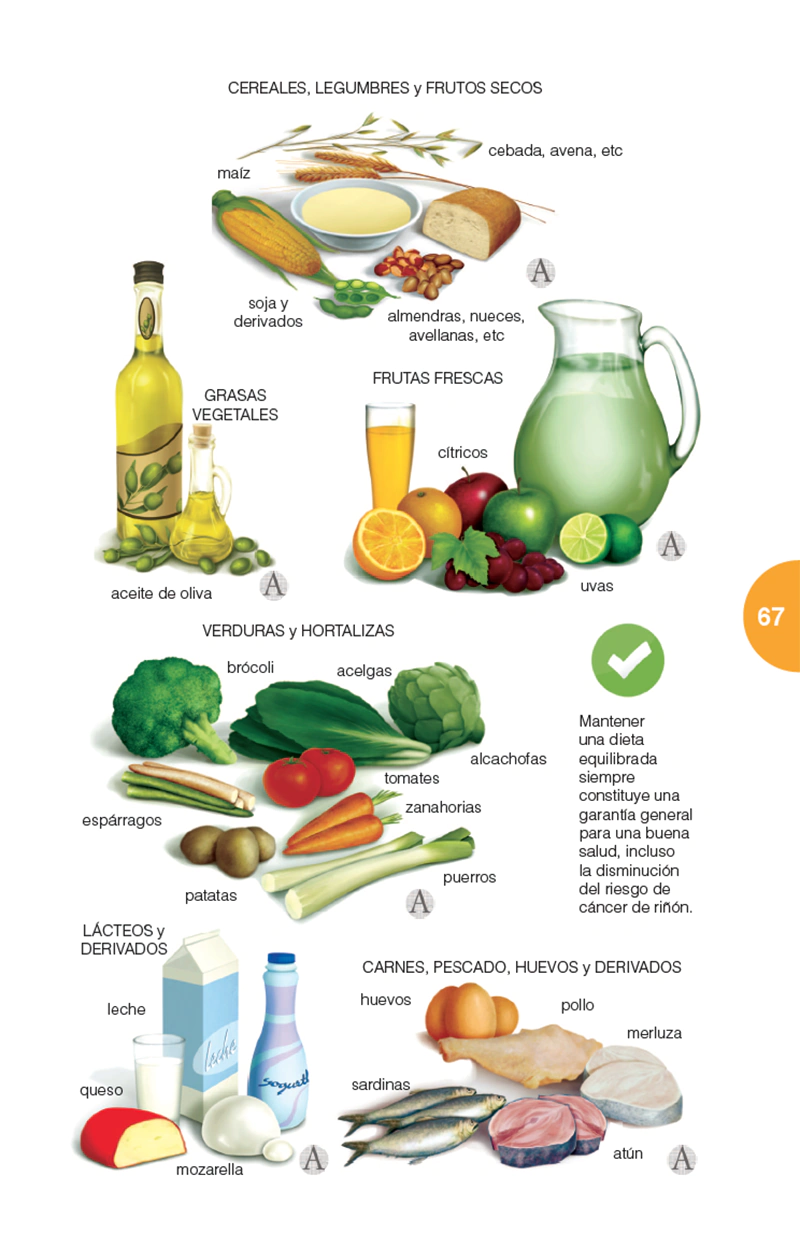

Este libro trata de manera concisa y precisa sobre esta patología y todo aquello que gira en torno a ella: qué es el cáncer de riñón, anatomía patológica, factores de riesgo, cuadro clínico, métodos diagnósticos, tratamiento, cuidados, prevención y un largo etcétera. Tanto el profesional de la medicina, como muchos pacientes y sus familiares encontrarán aquí una información inestimable y cumplida respuesta a mil preguntas que puedan formularse.